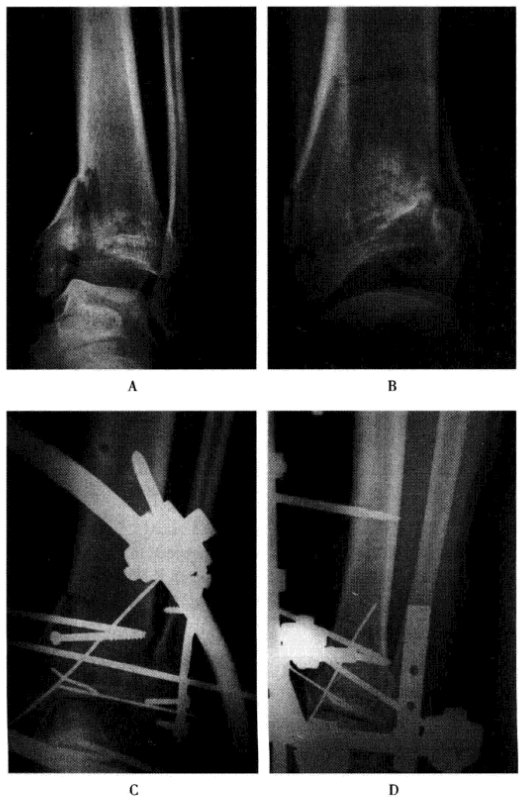

开放性胫骨远端Plion骨折组合外固定

A、B.治疗前;C、D.支架联合有限内固定治疗术后